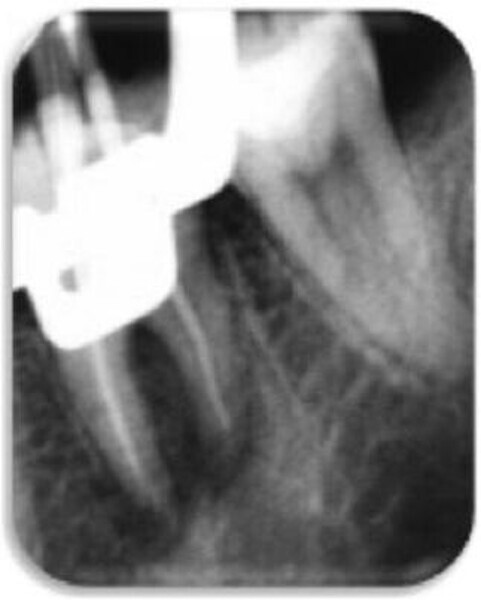

Leczenie endodontyczne autogennego przeszczepu zęba